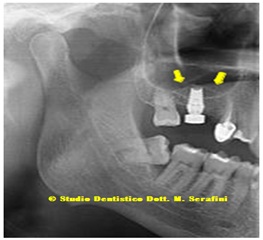

Control at six months on the right side and at 14 months on the left side, after finalization (Figure 27).

Figure 27: Control at six months on the right side and at 14 months on the left side.

Rx details in figure 28.

Figure 28: Left Side and Right Side note: the red arrows were the old sinus pavment and the yellow arrows, the new sinus pavment.